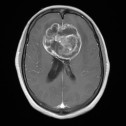

【见微知著】LVIS™ JR治疗大脑中动脉分支动脉瘤——河北省人民医院

徐国栋

姚文涛

徐国栋等2位作者

前天18:08